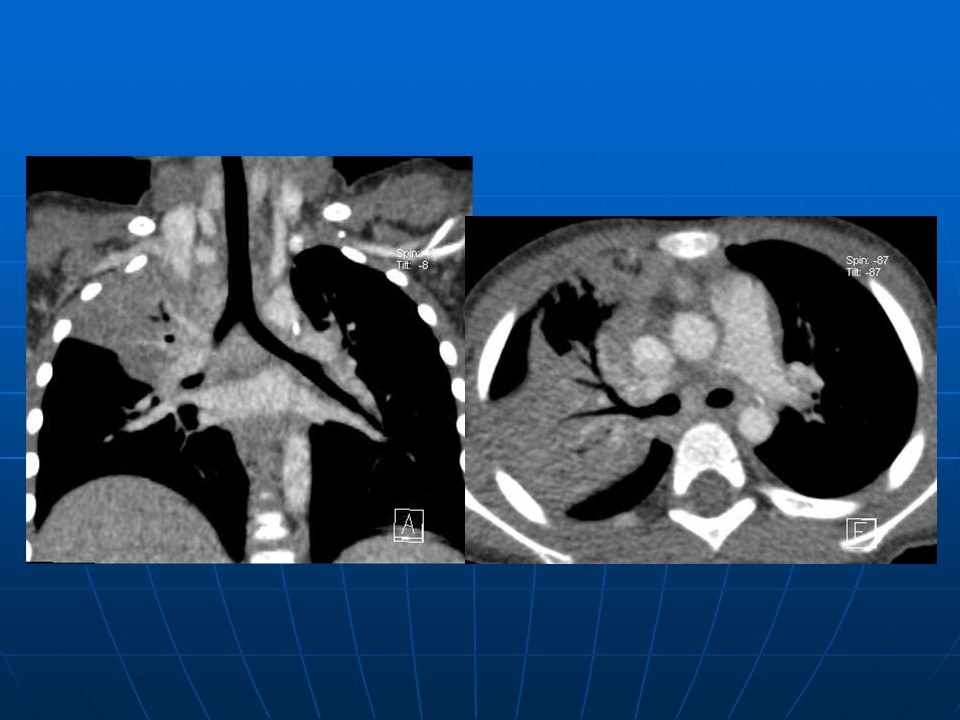

下一篇:【病例】肺动脉静脉畸形1例CT